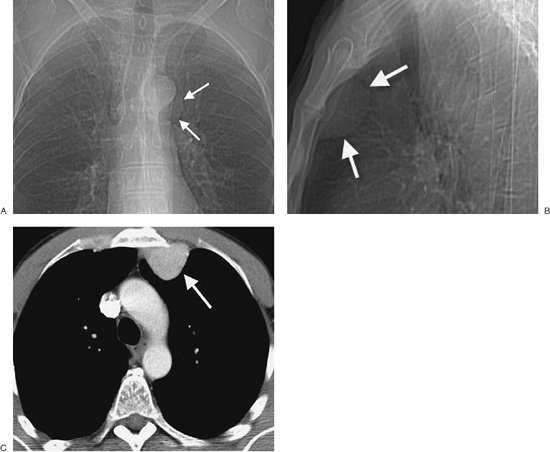

FIGURE 6-31. Bronchogenic cyst. A: PA chest radiograph of a 36-year-old woman shows an ovoid mass in the subcarinal area (arrowheads), a typical location for a bronchogenic cyst. B: Lateral view confirms the mass to be in a subcarinal location (arrows). C: CT scan shows that the mass is extremely dense throughout, consistent with milk of calcium (arrows).